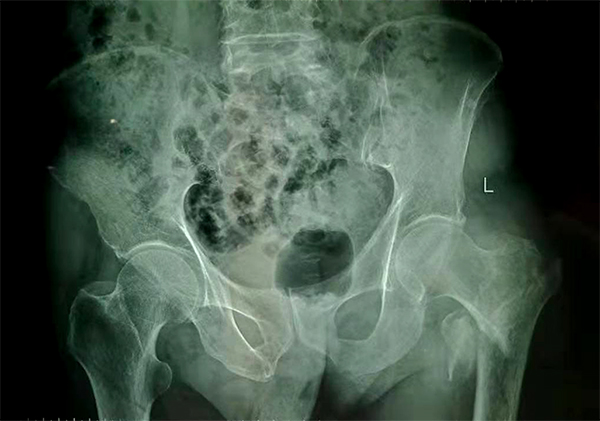

72歲的張爺爺半月前因摔傷致左下肢疼痛,當(dāng)時(shí)未予重視,在家臥床休養(yǎng)一段時(shí)間后出現(xiàn)骶尾部、左髖部及左外踝壓瘡,張爺爺?shù)募覍僭谒幏抠徺I了藥膏外涂創(chuàng)面,雖然創(chuàng)面已結(jié)痂,但是骶尾部、左髖部及左外踝壓瘡未見明顯好轉(zhuǎn),甚至還出現(xiàn)左外踝紅腫熱痛,皮膚破潰、滲液;于是來愛康醫(yī)院骨科就診。

經(jīng)檢查拍片診斷為左股骨粗隆間粉碎性骨折,收入骨科住院,張爺爺既往有“2型糖尿病”病史10余年,還有“腦梗塞”病史5年,導(dǎo)致左側(cè)肢體偏癱。